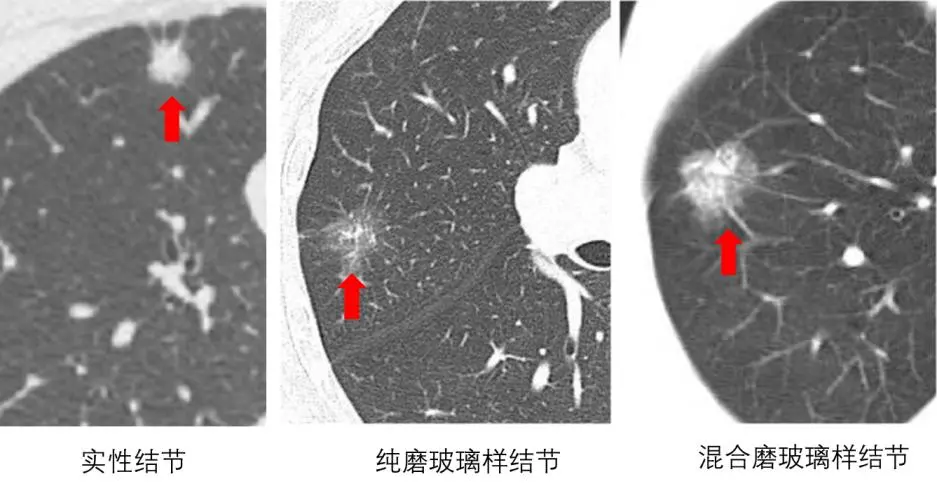

另外不同性质的结节在影像学上的表述不同,可以分为实性结节、部分实性结节和纯磨玻璃结节。

有文献统计,实性结节恶性率仅7%;像纯磨玻璃结节,恶性的概率相对大一点;混合磨玻璃结节(部分实性)恶性率为63%,纯磨玻璃结节恶性率为18%,大于20 mm的结节恶性率约80%。

但结节良恶性还需要靠专科医生判断,很多良性病变,也可以看到纯磨玻璃结节,比如炎症。如果是混合性的磨玻璃结节,恶性的概率则更大,当随着时间的推移,实性成分不断增多,很大程度上要考虑病灶恶变。